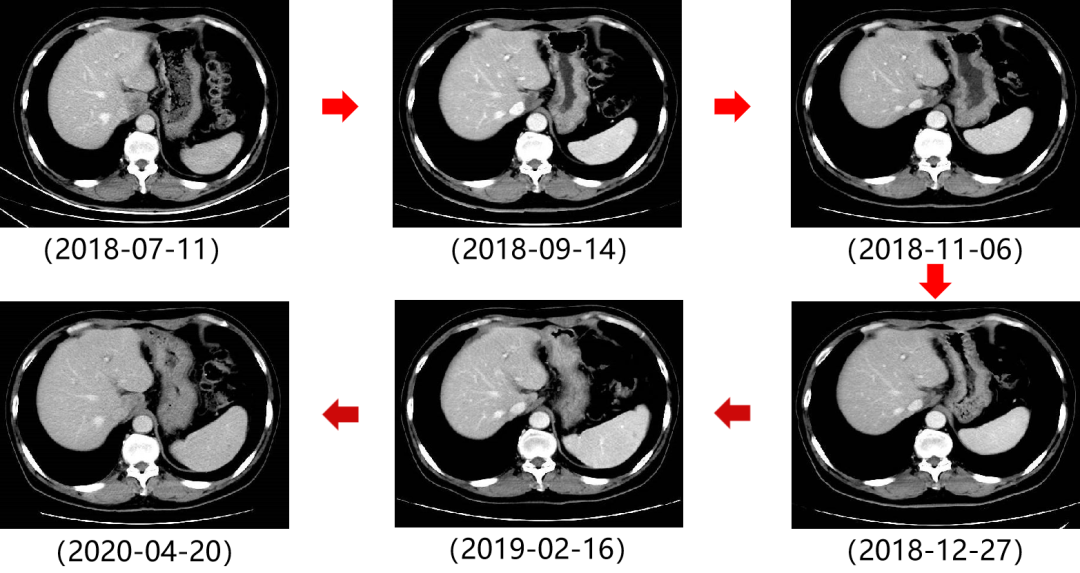

二 病例分享 专家简介 01 基本情况 患者:汪XX,男,63岁。身高 165cm;体重 65kg;体表面积 1.70m2;ECOG 1分。 主诉:反复解黏液血便3天。 对磁共振造影剂过敏,无食物、其他药物过敏史。既往史、个人史、婚育史、家族史均无特殊,无吸烟、饮酒史。 02 初诊病史 现病史:患者2017年3月初无明显诱因下解黏液血便,量中等,为鲜血,反复发作,无恶心、呕血、黑便、腹痛、腹泻、里急后重等不适。遂于2017年3月初就诊我院。 胸、腹、盆腔CT平扫+增强:乙状结肠肠壁明显增厚,肠腔狭窄,增强期强化明显;肝脏多发低密度病灶,增强期不规则强化,考虑乙状结肠癌伴肝脏多发转移。 03 治疗方案 【一线治疗】 2017-06-22 西妥昔单抗+FOLFIRI* Q2W×3 西妥昔单抗 900mg ivgtt D1; 5-氟尿嘧啶 0.6g iv D1,3.5g civ 48h; 亚叶酸钙 0.6g ivgtt D1; 伊立替康 280mg ivgtt D1。 第1疗程结束后黏液血便较前消失,过程顺利,耐受良好,无皮疹、腹泻等不良反应,治疗10疗程,疾病进展。 疗效评估-影像学(部分缓解,PR)。 2017-07-15 乙状结肠癌切除术* 手术记录:肿瘤位于乙状结肠,大小约4cm×3cm,未突破浆膜层,病灶周围可及数个稍肿大淋巴结,未及盆底种植结节。 手术过程顺利,术后恢复良好。 术后病理:(乙状结肠)中分化腺癌,浸润肠壁浆膜下层,两切缘阴性,未见脉管癌栓及神经束侵犯,LN 2/18(+) 2017-08-20 肝转移瘤切除术* 手术记录:肝脏肿瘤位于肝右叶,大小分别约2cm×1.5cm,1cm×1.2cm,其余肝表面未见异常结节,腹腔无腹水、无粘连。 手术过程顺利,术后恢复良好。 术后病理:(肝右叶病灶)中分化腺癌,结合临床病史,符合乙状结肠癌肝转移,肝组织切缘未见癌。 疗效评估-影像学(NED)。 2017-11-06 西妥昔单抗+FOLFIRI* Q2W×3 西妥昔单抗 900mg ivgtt D1; 5-氟尿嘧啶 0.6g iv D1,3.5g civ 48h; 亚叶酸钙 0.6g ivgtt D1; 伊立替康 280mg ivgtt D1; 过程顺利,无皮疹、腹泻等不良反应。每疗程后均予PEG-CSF预防性升白,耐受良好。 疗效评估-影像学(病情进展,PD1)。 胸、腹、盆腔CT平扫+增强:肝左外叶低密度灶,增强期不规则强化,结合病史,考虑结肠癌肝转移,余未见明显异常。 【二线治疗】 2018-03-06 肝左外叶肿瘤切除术* 术中探查见:肿瘤位于肝左外叶,质硬,边界不清,余肝脏表面未见异常结节灶,腹盆腔无腹水。 手术过程顺利,术后恢复良好。 术后病理示:(肝左叶)中分化腺癌,结合临床病史,符合结肠腺癌肝转移。 2018-04至2018-07 卡培他滨+奥沙利铂* Q3W×5 卡培他滨 1.5g BID D1-14; 奥沙利铂 200mg ivgtt D1。 过程顺利、耐受良好,无腹泻、神经毒性等不良反应。 疗效评估-影像学(病情进展,PD2)。 胸、腹、盆腔CT平扫+增强:肝尾状叶结节状异常密度灶,增强期不规则强化,结合病史,考虑结肠癌肝转移,余未见明显异常。 2018-07至2020-04 贝伐珠单抗+卡培他滨* Q3W×21 贝伐珠单抗 500mg ivgtt D1; 卡培他滨 1.5g BID D1-14。 过程顺利、耐受良好,期间曾出现II度腹泻,对症治疗后可恢复正常。无血压升高、出血、蛋白尿、手足皮肤反应。 疗效评估-影像学(最佳疗效,PR)。 疗效评估-影像学(病情进展,PD3)。 腹腔镜肝尾状叶切除术+腹腔粘连松解术* 术中探查见:肿瘤位于肝尾状叶,质硬,边界不清,余肝脏表面未见异常结节灶,腹盆腔无腹水。 手术过程顺利,术后恢复良好。 术后病理示:(肝尾状叶)中分化腺癌,结合临床病史,符合结肠腺癌肝转移。 2020-06至2021-09 贝伐珠单抗+卡培他滨* Q3W×16 贝伐珠单抗 500mg ivgtt D1; 卡培他滨 1.5g BID D1-14。 过程顺利、耐受良好,期间曾出现II度腹泻,对症治疗后可恢复正常。无血压升高、出血、蛋白尿、手足皮肤反应。 疗效评估-影像学(NED)。 疗效评估-影像学(NED)。 【三线治疗】 2021-12-16 西妥昔单抗+TAS-102* Q3-4W×2 西妥昔单抗 900mg ivgtt D1; TAS-102 60mg BID D1-5,8-12。 过程顺利、耐受稍差,期间出现II度骨髓抑制(三系减少),对症治疗后可恢复正常。无皮疹、输液反应等。 疗效评估-影像学(部分缓解,PR)。 04 治疗小结